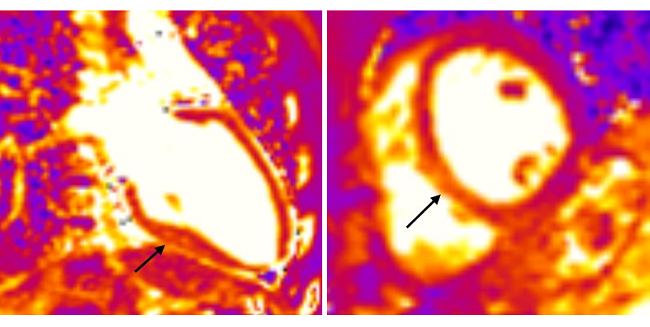

Top Stories in Cardiology: June 2020This month, Julia Grapsa and Mary Norine Walsh describe the many ways COVID-19 affects the heart. |